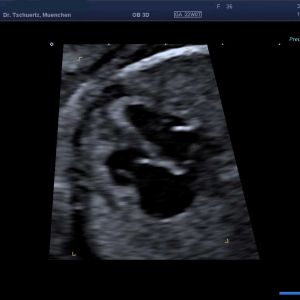

Schwerwiegende komplexe Herzfehler können schon im 1. Trimenon im Rahmen der frühen Fehlbildungsdiagnostik erfasst werden – optimaler Zeitpunkt zur Diagnostik von Herzfehlern ist die 20. - 22. SSW in Rahmen der Feindiagnostik (Organultraschall). Beurteilt werden die Lage des Herzens, die Herzkammern, die Herzklappen, die dem Herzen entspringenden Gefäße und der Herzrhythmus.